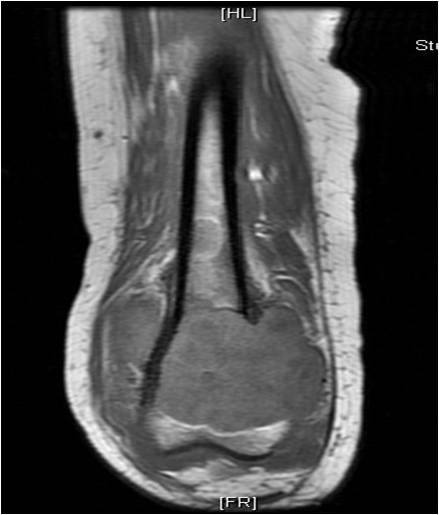

On radiographs, most MFHs of Bone are located in the metaphysis and present as purely osteolytic permeative lesions without a periosteal reaction and without mineralization (Fig. 1 &2). On MR images, MFH of Bone has ill-defined margins usually with cortical destruction of bone and extension into the soft tissues. It is usually hypo- or isointense to muscle on T1-weighted images (Fig. 3) and heterogeneous high intensity on T2-weighted images (Fig. 4-6).

Fig. 3: Coronal T1-weighted MR image of a Malignant Fibrous Histiocytoma of Bone demonstrates a lesion with intermediate signal similar to muscle in the distal femur. The lesion extends into the surrounding soft tissues.